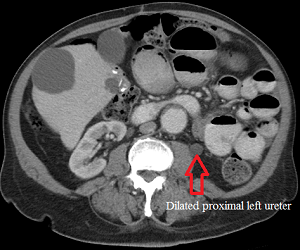

Axial CT scan of the abdomen before left ureteral stenting showing dilated left ureter.